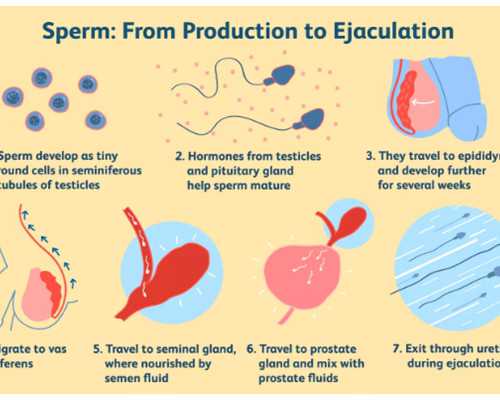

導致女性不孕的病因有很多,如:女性本身患有婦科炎癥、卵巢功用不全、內分泌失調等,病因品種不同,其治療辦法有所不同,自然治療費用也不盡相同,如果想節省煙臺山醫院試管助孕費用,建議對癥治療后再助孕。

不同年齡階段的女性做試管嬰兒,其用藥量也會不一樣。由于,隨著女性年齡的增長,卵巢功用逐步衰退,所以在做試管嬰兒時,年齡偏大的女性用藥量會相對較多,進而增加了相應的費用。

5、選對促排方案

不同促排卵計劃用藥品種及用藥量不同。相比而言,微刺激計劃、自然周期計劃、黃體期計劃由于用藥較少,因而要求的治療費和藥費低于其他計劃。試管嬰兒醫院關于排卵計劃的制定一定是依據就診者目前的身體狀況,選擇有利的計劃進行。